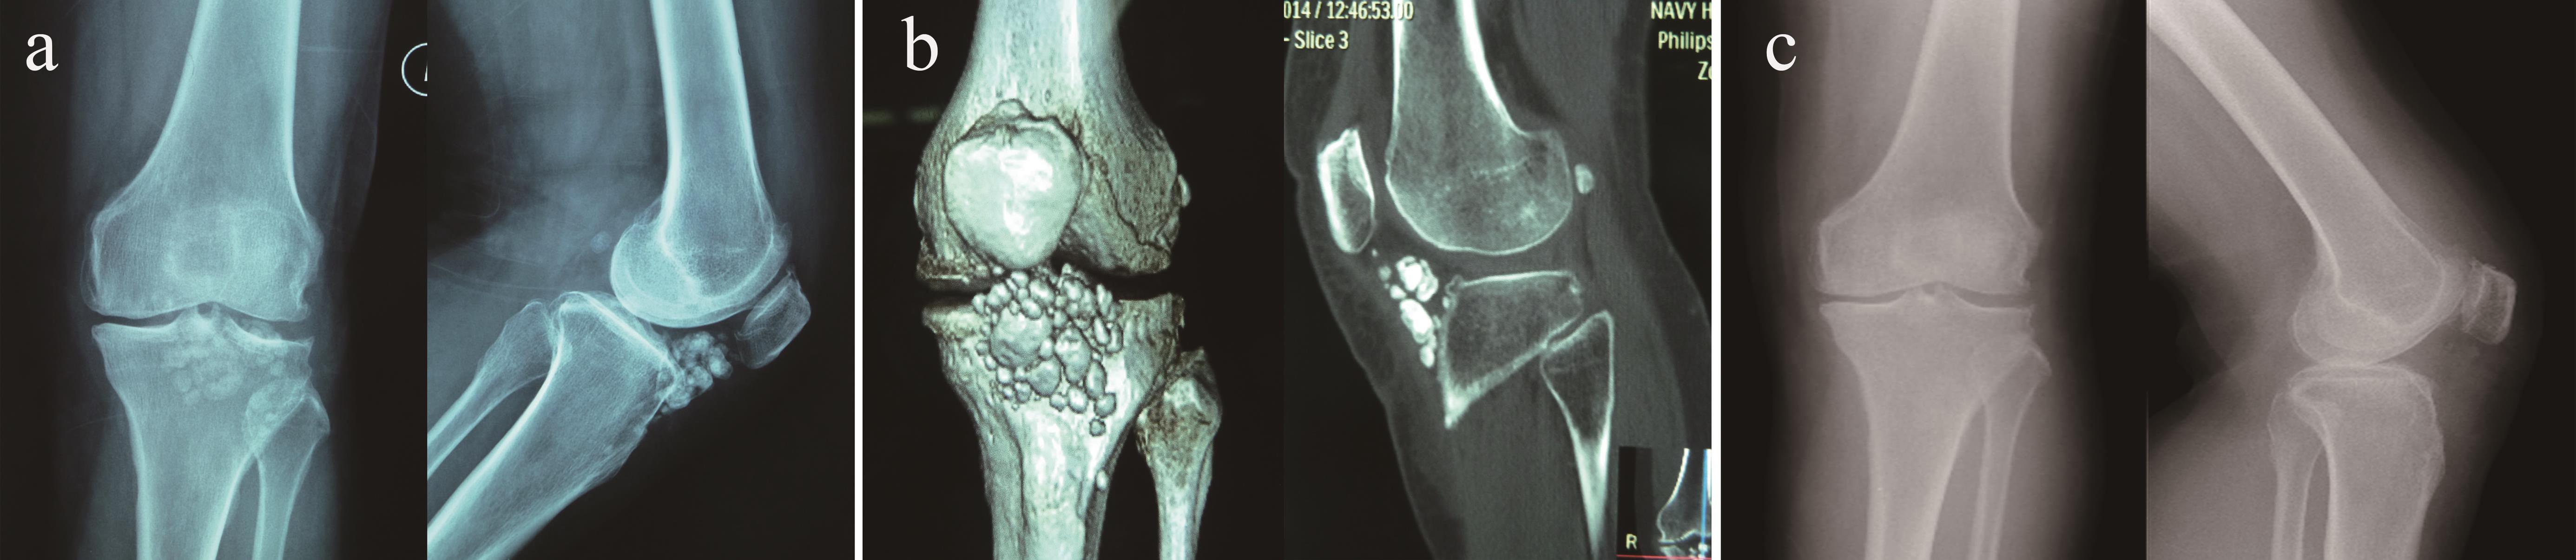

From www.researchgate.net

Elbow synovial chondromatosis. Preoperative radiology showed (a Synovial Osteochondromatosis Elbow Treatment treatment for synovial chondromatosis typically involves surgery to remove the loose bodies of cartilage. either conservative treatment or surgery can be used to treat synovial chondromatosis of the elbow. synovial chondromatosis (osteochondromatosis or synovial chondrometaplasia) also known as reichel. the pain, swelling, and mechanical symptoms of synovial chondromatosis and its generation of. arthroscopic treatment of. Synovial Osteochondromatosis Elbow Treatment.

Elbow synovial chondromatosis. Preoperative radiology showed (a Synovial Osteochondromatosis Elbow Treatment arthroscopic treatment of elbow synovial chondromatosis. the pain, swelling, and mechanical symptoms of synovial chondromatosis and its generation of. removal of loose bodies and synovectomy for the management of synovial osteochondromatosis of the elbow is. either conservative treatment or surgery can be used to treat synovial chondromatosis of the elbow. synovial chondromatosis (osteochondromatosis or synovial. Synovial Osteochondromatosis Elbow Treatment.